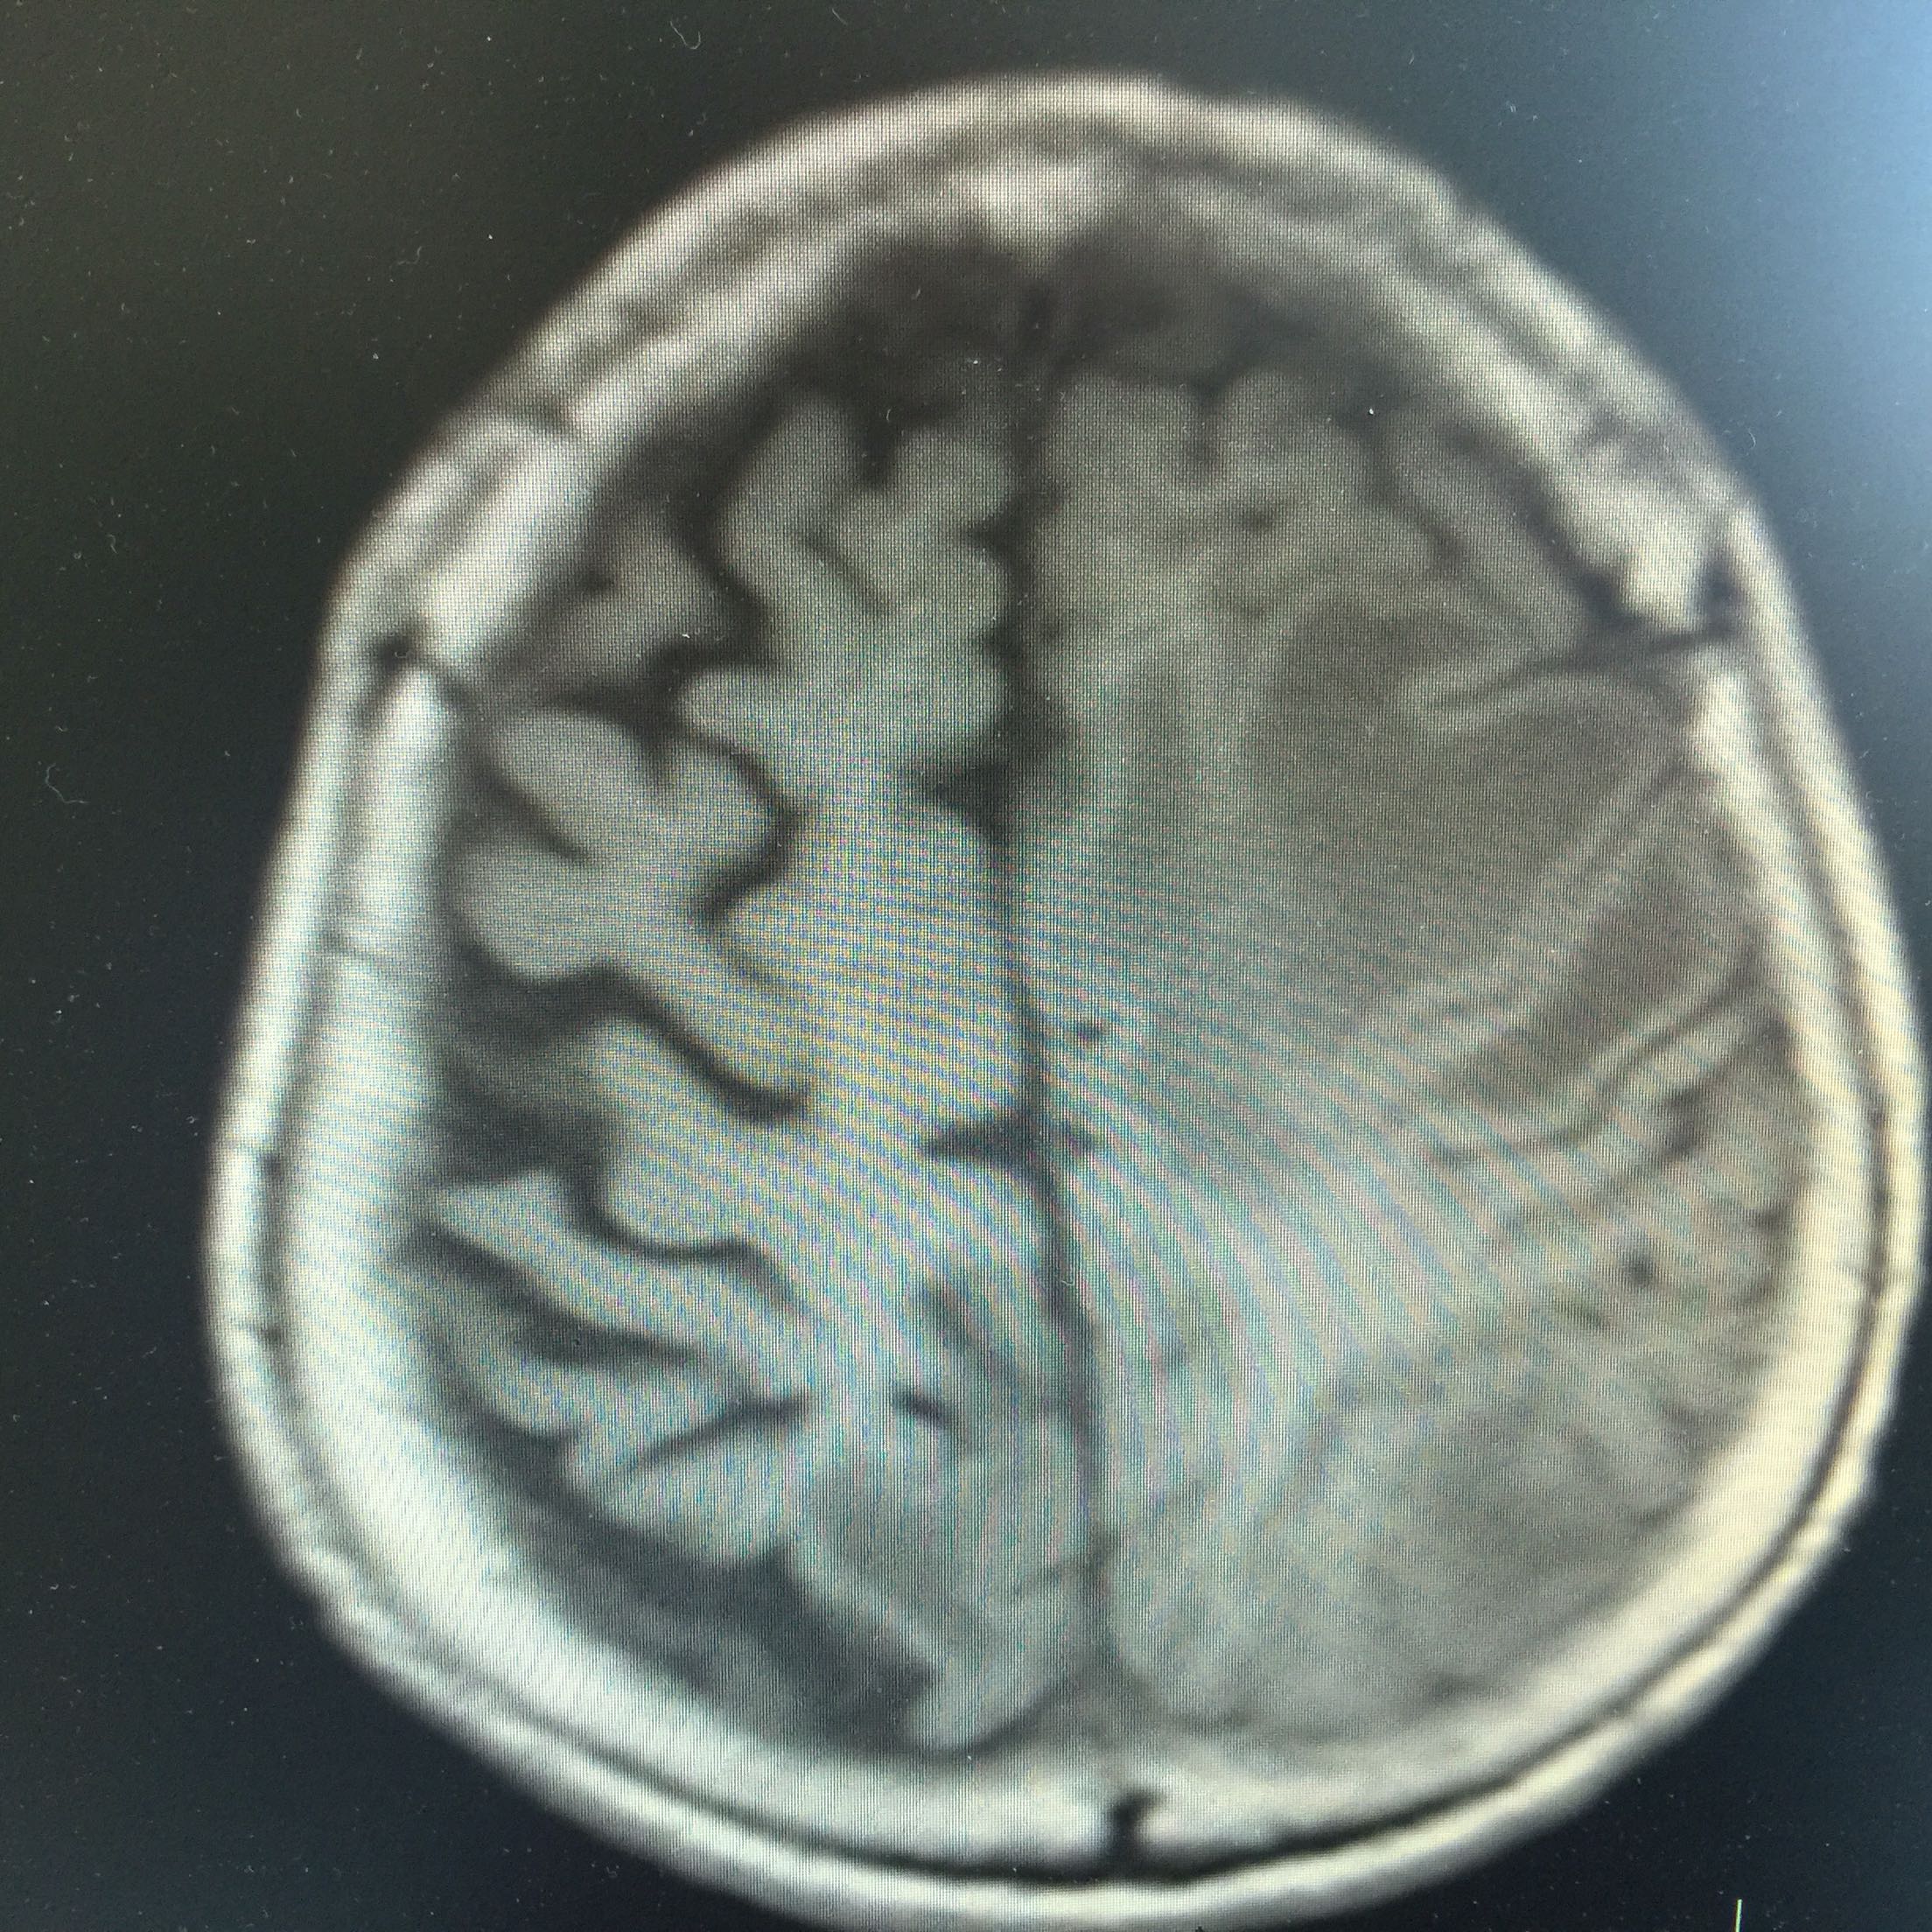

1.女,81岁,以“右侧肢体无力3天”入院。 2.现病史:3天前无诱因出现右侧肢体无力,右上肢抬举费力,右下肢步行拖拉,无抽搐,无意识障碍! 3.既往史:2016年肺穿刺活检,免疫组化为腺癌!已合并第五、六椎体转移、左肾上腺转移,行灌注介入治疗。

查体:血压:130/80mmHg,两肺呼吸音清,未闻及啰音,心率98次/分,律齐,未及杂音,双下肢无水肿。神经系统查体:意识清,双侧瞳孔等大正圆,直径约3.0mm,对光反射灵敏,无面舌瘫,右侧肢体肌力4级,腱反射减弱,Babinski征R+L-。

左肺腺癌 骨转移、双肺门及纵膈淋巴结转移、左肾上腺转移、脑转移! 治疗:对称、支持治疗!